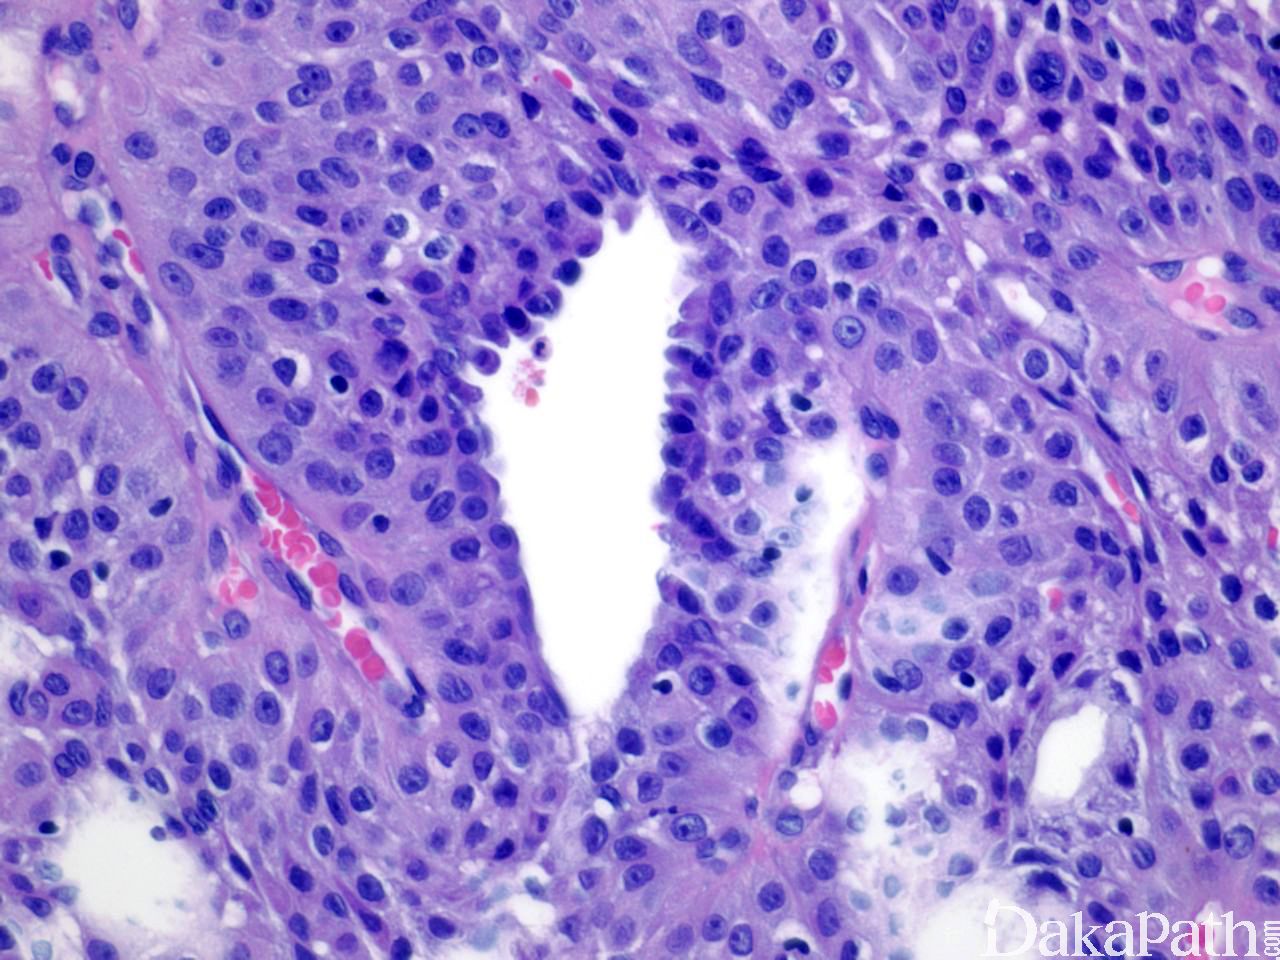

4. 肿瘤由一致的嗜酸细胞和胞质透明富含糖原胞质透明的细胞构成,两者比例因人而异,部分区域伴鳞状分化甚至角化珠形成;

5. 瘤体中有汗腺小管结构,可扩张呈囊性区域,囊内充满粉染无结构物,管腔或囊内衬立方导管细胞或柱状分泌细胞,核分裂少见。